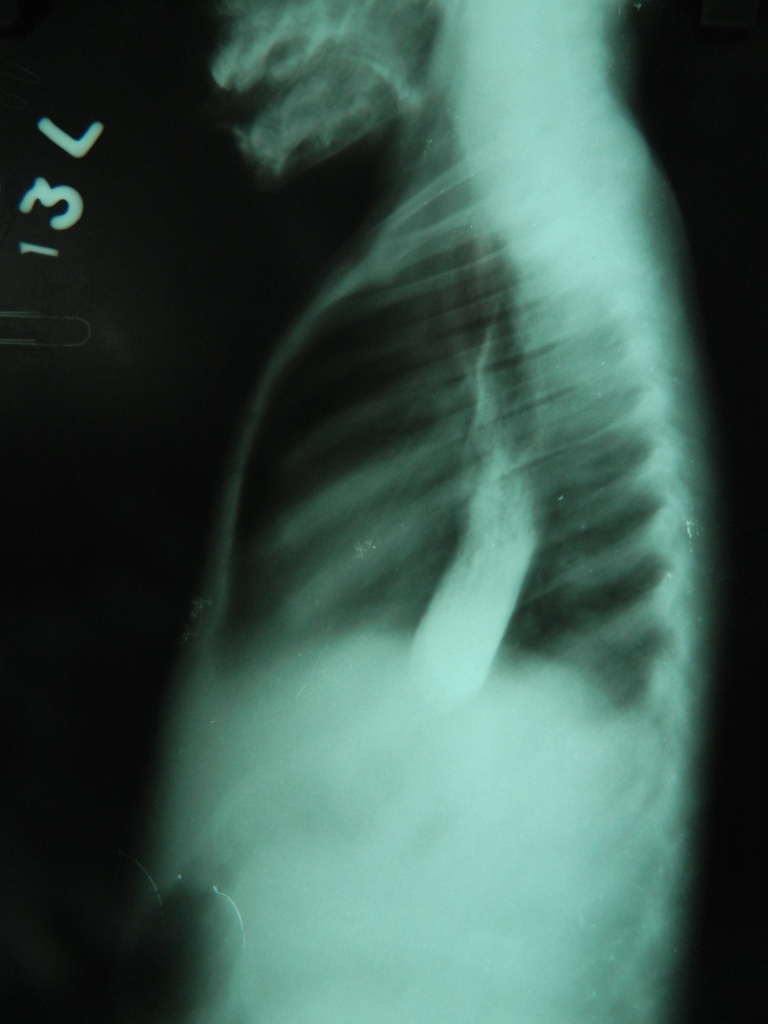

- Case 1(a)- Lateral view of Barium esophagogram